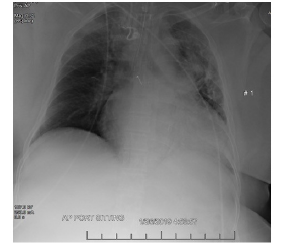

Electrocardiogram revealed possible left atrial enlargement and left ventricular hypertrophy, indicative of progressive left ventricular failure. Her electrocardiogram also showed anterolateral T-wave inversion (Figure 1). On telemetry, she had a normal sinus rhythm with a ventricular rate of 69. Transthoracic echocardiography revealed an estimated left ventricular ejection fraction of 25%. Additional findings include grade III diastolic dysfunction with elevated left atrial pressure, severe left atrial enlargement with severely abnormal left atrial ventricular index, severe right ventricular enlargement with normal function, right ventricular base measuring 5.6 cm, severely enlarged right atrium, severe mitral regurgitation, mitral regurgitation grade severity of 0.5 cm2, moderate to severe tricuspid regurgitation, and her inferior vena cava barely collapsed during inspiration suggesting elevated right atrial and ventricular end-diastolic pressures (Figure 2) Chest x-ray (Figure 3) revealed a nonspecific right infrahilar opacity suggestive of atelectasis or an infiltrative process, in addition to mild-to-moderate cardiomegaly.